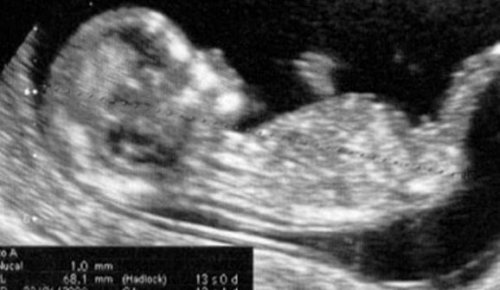

妊娠すると、エコーなどを使った診察が行われます。

厚生労働省が定めているエコーによる妊婦検診の標準回数は、妊娠初期から23週の間に2回、24から35週の間に1回、妊娠36週から出産の間に1回となっています。ですが、病院の方針や両親の希望、母親の体調や状況、赤ちゃんの発育状態によって異なります。

診察の回数は、初期のころに比べると一時的にですが、頻度が少なくなります。

胎児の成長を確認するため、月に1回の診察は必ず受けましょう。もちろん母体の不具合がある場合も診察は必要です。